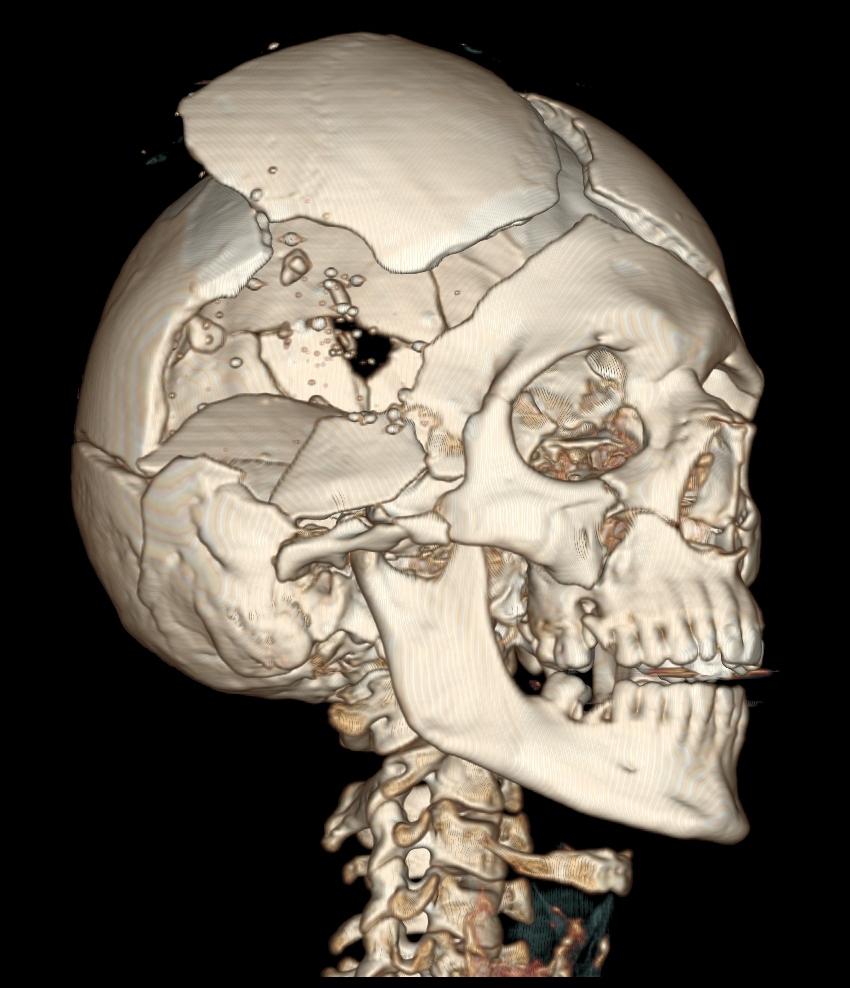

虽然被*弹子**击中是一件很可怕的事情,但是也不是就会有那么大的死亡率,据美国枪击创伤研究机构的数字表明,在现有的医学条件下,即便是被*弹子**直接击中头部,生存率仍然有9%,心脏被击中有3%,而一般性的枪击,你实际上会有80-95%的生存机会,有的时候会超过95%,但是这个利率是取决于能不能快速止血,或者是快速降低出血量,同时又能补充血液,同时还有一个重要的因素,那就是其实你的身体的80%的部位是不致命的!